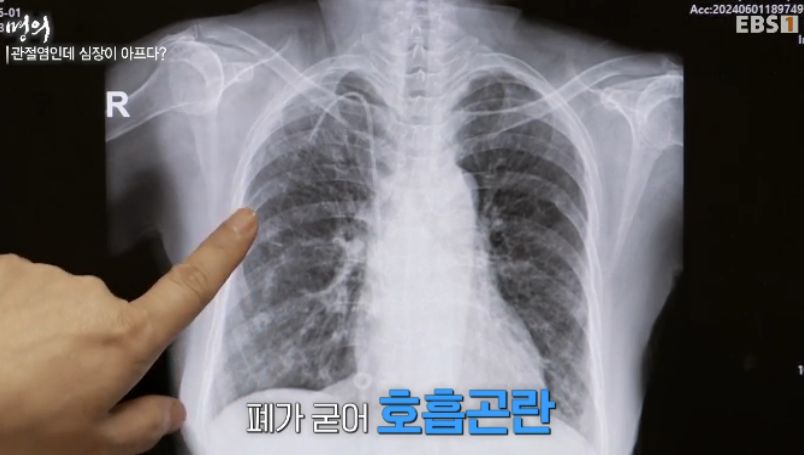

관절염인데 심장이 아프다?

류마티스 관절염의 합병증 = 온 몸.

류마티스의 합병증.

류마티스는 관절병이지만, 전신 합병증을 만든다.

심근경색, 뇌경색이 많이 걸린다.

폐.. interstitial pneumonia 폐렴, 폐섬유화. 숨을 못 쉬게 된다.